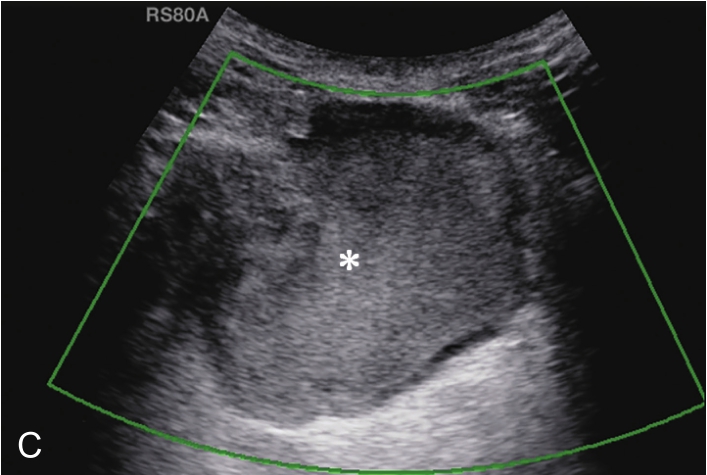

▲ 图 2-1-12(续)

C.彩色多普勒显示囊性团块(星号)内无血流信号;D.超声造影显示囊性团块内呈无增强;E.冈上肌腱完全断裂,关节腔积血(星号);F.超声引导下穿刺液体抽吸及药物注射治疗,箭头示穿刺针